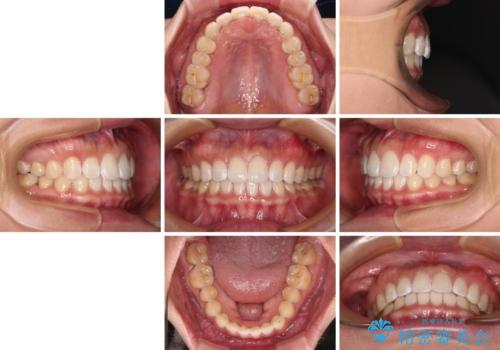

【モニター】前歯のすきっ歯をインビザラインで改善

- 1年1ヶ月

すきっ歯はあっという間に後戻りを起こすので、可及的に後戻りを防止するために、上下前歯部を舌側からワイヤーで固定しています。

通常は下顎前歯のみに行っていますが、空隙歯列弓では上顎でも行っています。